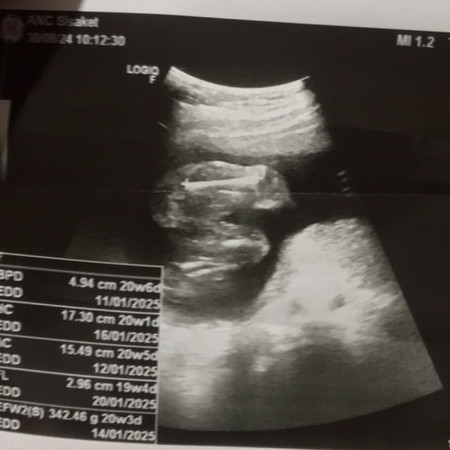

ช่วยดูเพศลูกให้ทีค่ะพอดีดูยังไงก็ดูไม่ออก😅

หมอบอกได้ผู้ชายแต่เราดูยังไงก็ดูไม่ออกค่ะ

เราว่า หญิง ถ้าชาย จู๋จะต้องยื่นออกมาค่ะแม่